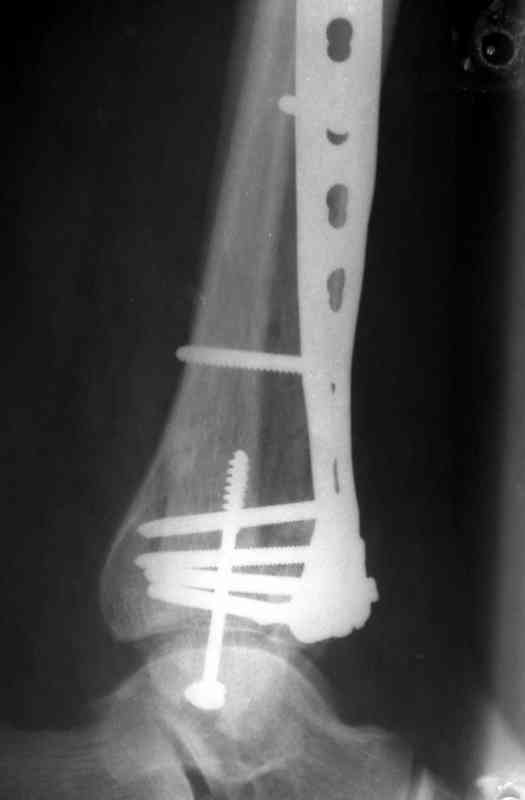

На рентгенограммах типичный перелом пилона по типу С-3. есть опыт до 100 открытых опреаций у нас в клинике. 20 примерно в год. Принцип один -все внутрисуставные переломы нуждаются в открытой репозиции и внутренней стабильной фиксации. При поступлении КТ не надо, так как получается только нагромождение костей. Истинной картины нет. Главное восстановить длину малоберцовой кости - это ключ к успеху. При поступлении меньше всего надо думать о сосудистых расстройствах, т.к. сама операция и репозиция даже сначала частичная даёт улучшение сосудитых нарушений. Причём очень быстро. Операция в 2этапа. При поступлении доступ позади наружной лодыжки, причём обязательно. После этого репозиция малоберцовой кости и фиксация пластиной 1/3 трубки под винт 3,5. Дренаж и любой аппарат наружной фиксации. Затем после спадения отёка на 5-7-10 день аппрат снимается и дугообразный разрез спереди от медиальной лодыжки 10-12 см. Главной чтобы расстояние между 1 и вторым разрезом было не меньше 7-8 см. Тогда не будет некрозов лоскутов. Таранная кость используется как матрица на неё укладываются отломки и фиксируются пицами. Ренг-контроль. Отломки лежат все отдельно, но ничего не высыпется. При переломах С-3 всегда нужна костная пластика (из крыла). Фиксация пластиной лист клевера простой или LCP. Гипс не нужен. Дренаж до 48 часов. Операция длится 3-4 часа обязательно без жгута. Посылаю примерно такой же случай.